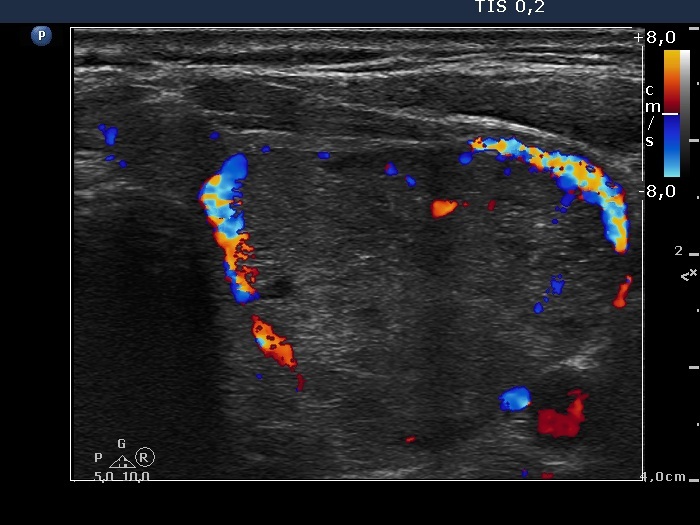

Ultrasonography. The right thyroid was intact. A large nodular area occupied almost the entire left thyroid. It was composed of moderately hypoechogenic, cystic, echonormal and hyperechogenic discrete lesions. The whole lesion was surrounded with an incomplete halo and presented a type 2 vascular pattern.